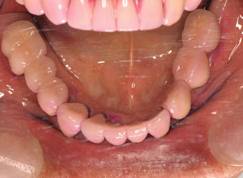

上顎

下顎

上部構造装着後6年。ハイブリッドレジンを使用したため、少し艶がなくなってきました。上部構造の材料には金属、ハイブリッドレジン、セラミックなどがあります。セラミックはきれいですが欠けやすいため、最近はフルジルコニアを使っています。

上顎 少しすり減ってきました。

下顎。12か月に一度メインテナンスをしています。